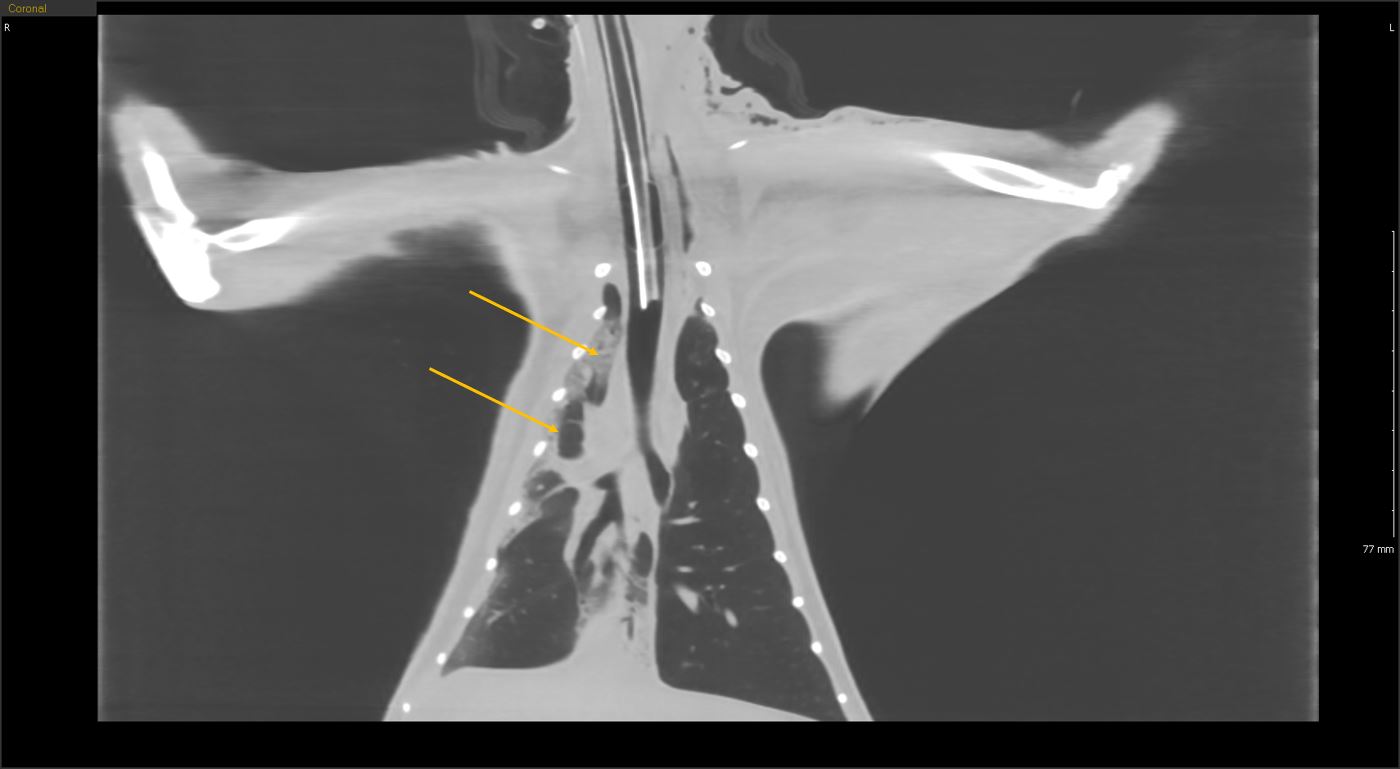

흉부심장 및 대형 혈관, 폐 실질 및 기관, 기관지

흉부 CT

흉부